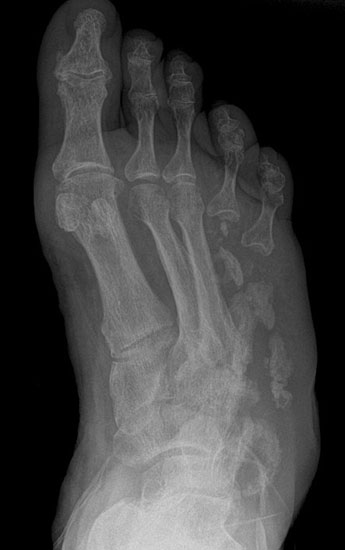

Eitrig-infiziertes Ulkus an der Spitze der 2. Zehe als Indikation zur Endgliedamputation.

Abbildung 13

Chronisches Ulkus mit Infektion (Abb. 13).